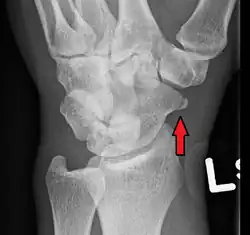

A subtle scaphoid fracture

A more obvious scaphoid fracture on a scaphoid view X ray

Radiolucency around a 12 days old scaphoid fracture that was initially barely visible.[11]

Fracture of the tubercle of the scaphoid bone of the wrist